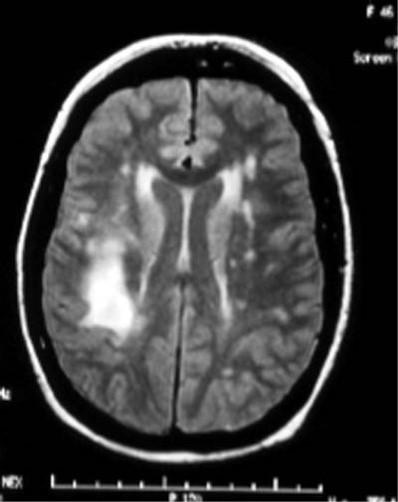

what is this on the MRI

demyelinization

what is gliosis associated with

demyelinazation and edema

what is edema associated with

demyelininzation and gliosis